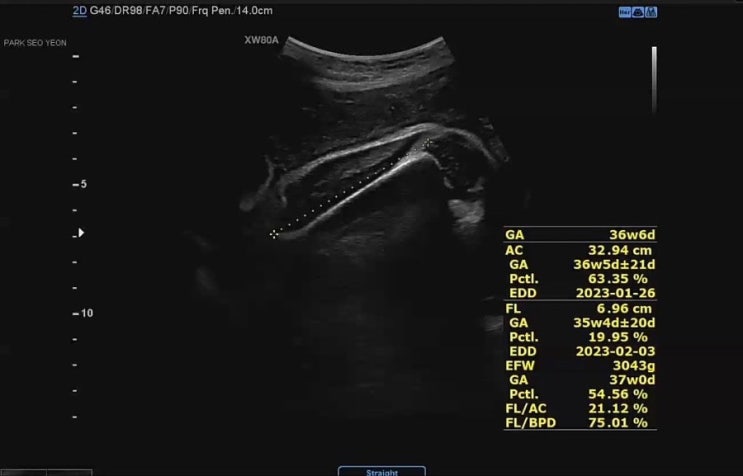

[태교일기] 임신36주차 | 산부인과 첫 내진검사 | 균검사 | 분만방법상담